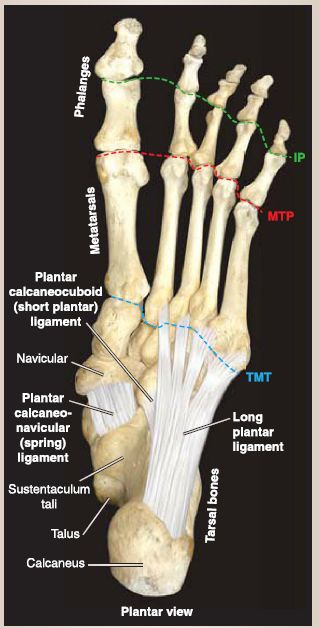

Joints of the foot are numerous and include the subtalar, talocalcaneonavicular, calcaneocuboid, cuneonavicular, tarsometatarsal, intermetatarsal, metatarsophalangeal, and interphalangeal joints (Fig. 9). Figure 10 shows plain film of the foot and bones.

Figure 9: Foot joints. Supporting ligamentous structures. IP = interphalangeal joints,

MTP = metatarsophalangeal joints, TMT = tarsometatarsal joint.

2. Ligaments: Major supporting ligaments of the foot include the plantar calcaneonavicular ligament (spring ligament), long plantar ligament, and the short plantar ligament (plantar calcaneocuboid ligament). These ligaments passively support the longitudinal and transverse arches of the foot.